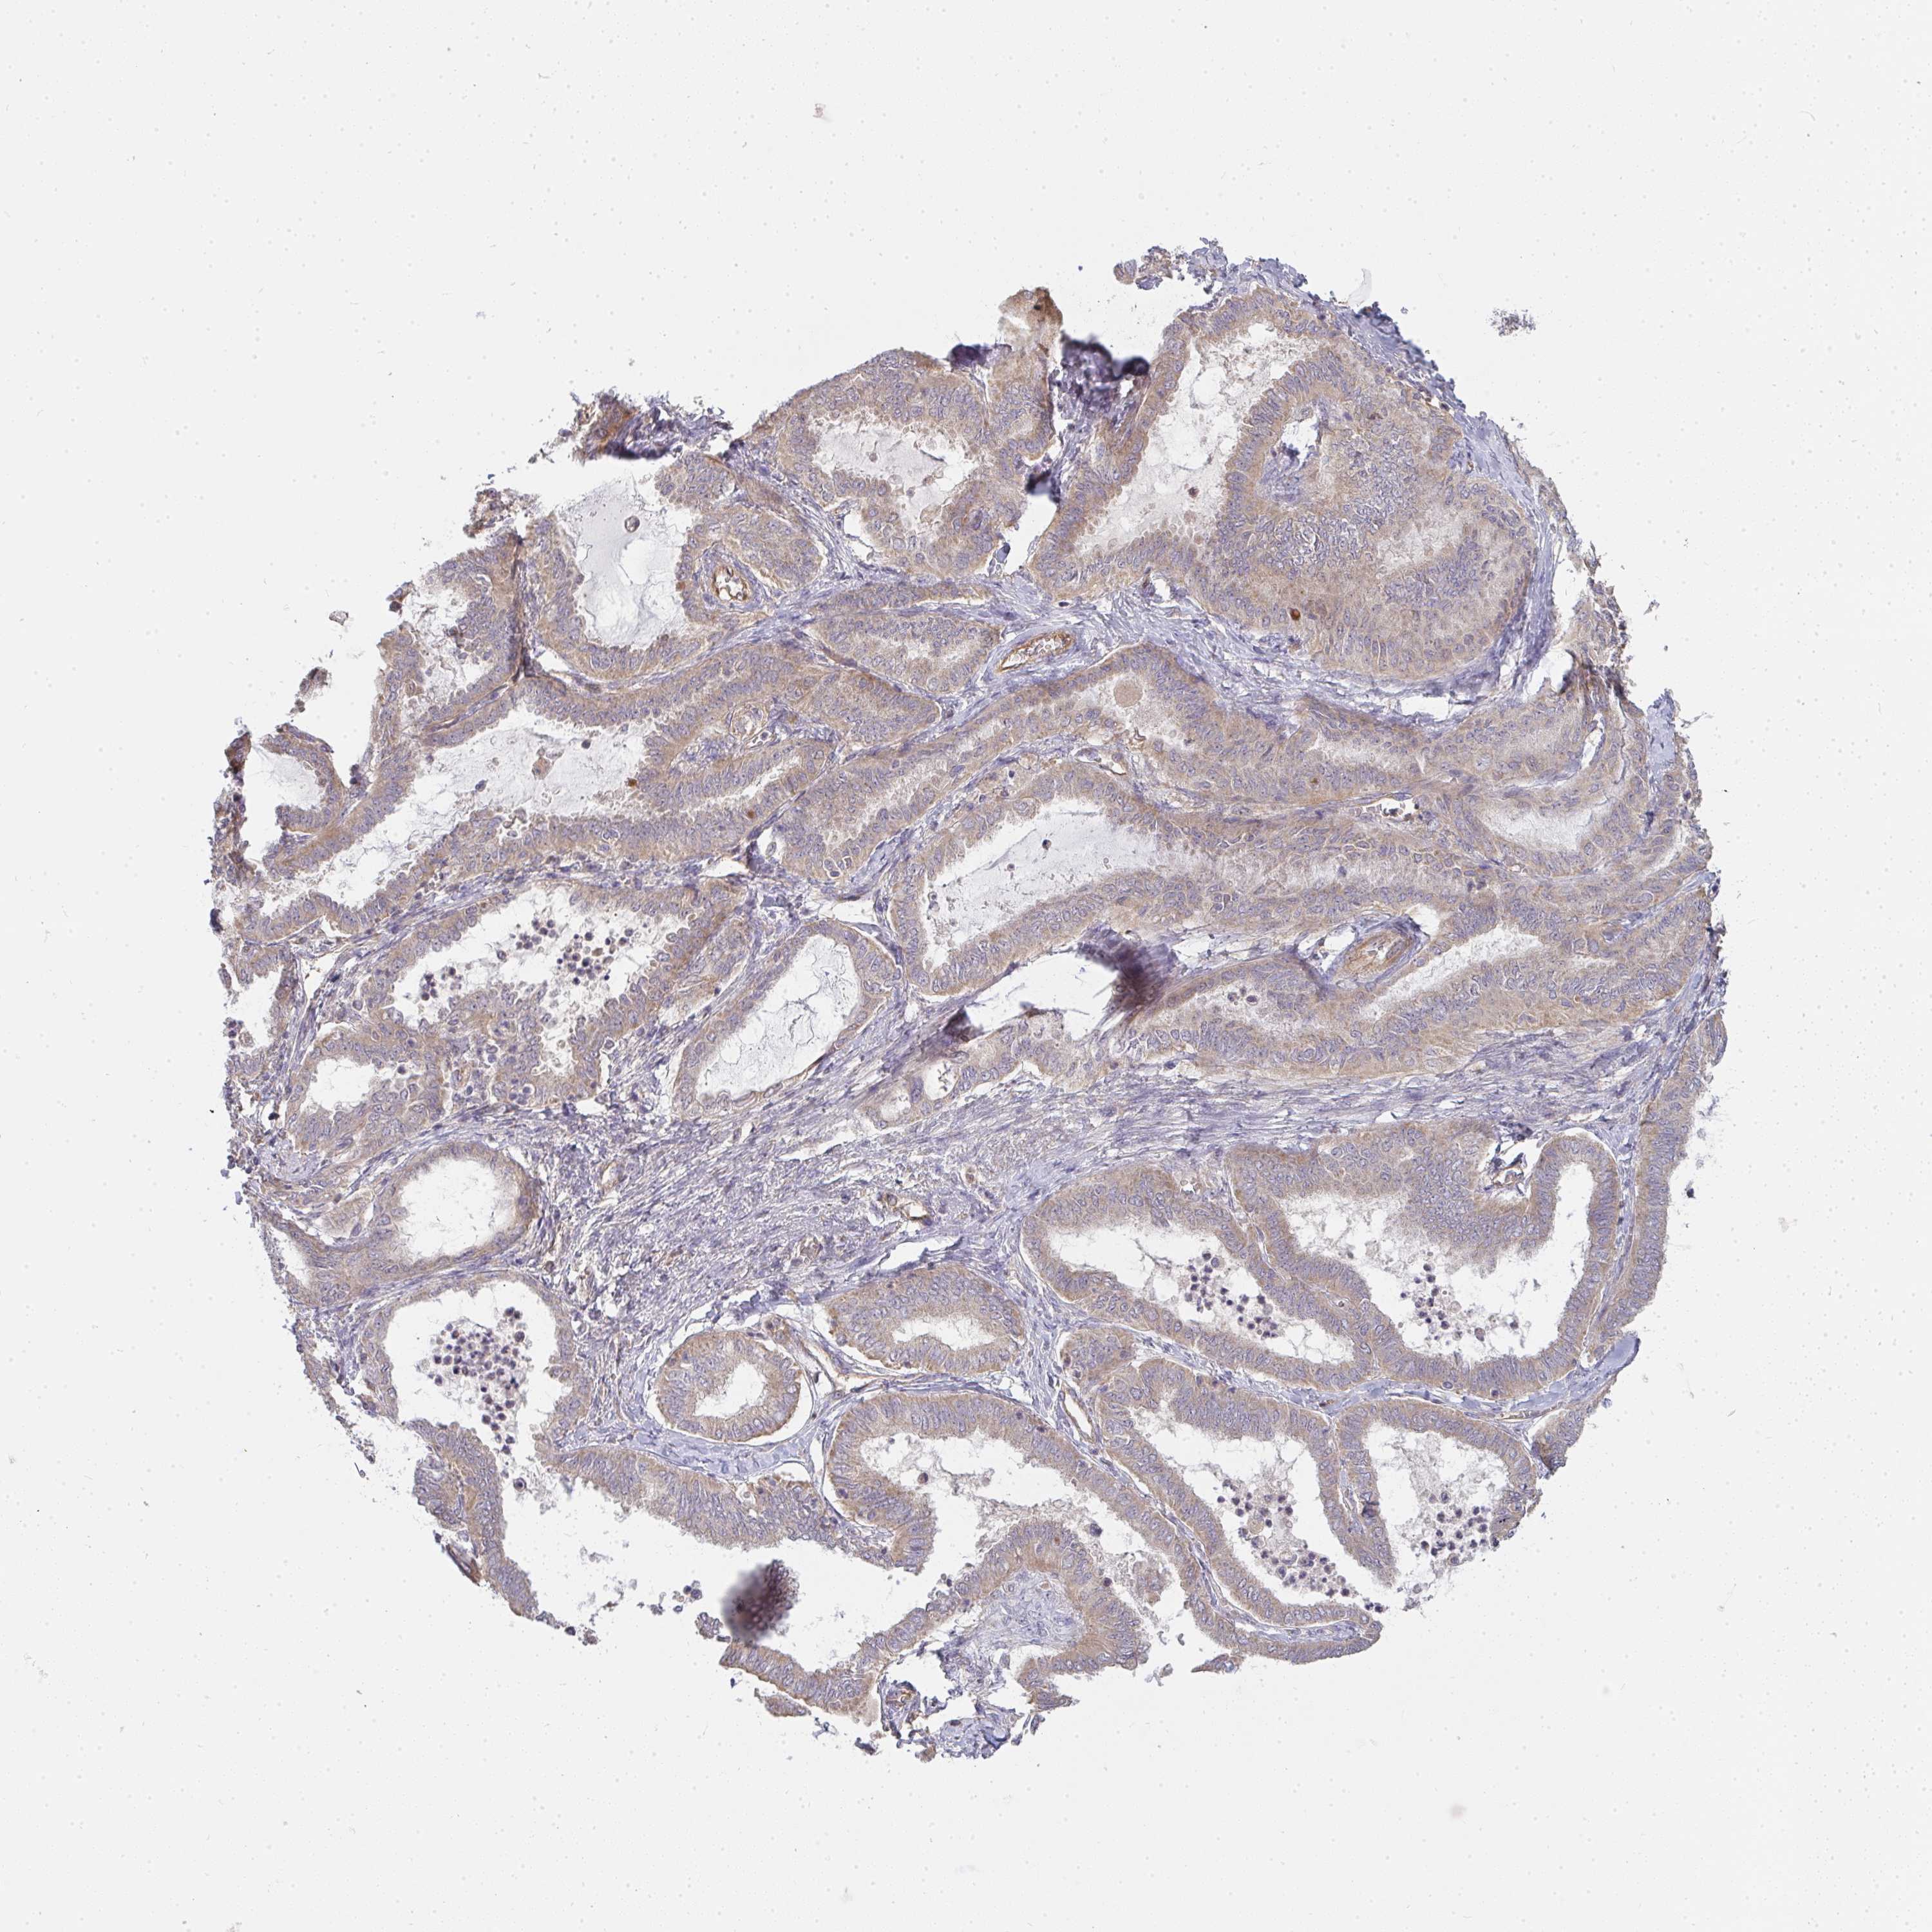

OVARIAN CANCER - Protein expressioni

A mouse-over function shows sample information and annotation data. Click on an image to view it in a full screen mode. Samples can be filtered based on level of antibody staining by selecting one or several of the following categories: high, medium, low and not detected. The assay and annotation is described here.

Note that samples used for immunohistochemistry by the Human Protein Atlas do not correspond to samples in the TCGA dataset.

Antibody stainingi

Antibody staining in the annotated cell types in the current human tissue is reported as not detected, low, medium, or high, based on conventional immunohistochemistry profiling in selected tissues. This score is based on the combination of the staining intensity and fraction of stained cells.

Each image is clickable and will lead to virtual microscopy that enables deeper exploration of all samples and also displays staining intensity scores, fraction scores and subcellular localization as well as patient and tissue information for each sample.

Antibody HPA058284

Antibody CAB020701

Staining

High

Medium

Low

Not detected

Intensity

Strong

Moderate

Weak

Negative

Quantity

>75%

75%-25%

<25%

None

Location

Nuclear

Cytoplasmic/membranous

Cytoplasmic/membranous,nuclear

Cystadenocarcinoma, mucinous, NOS